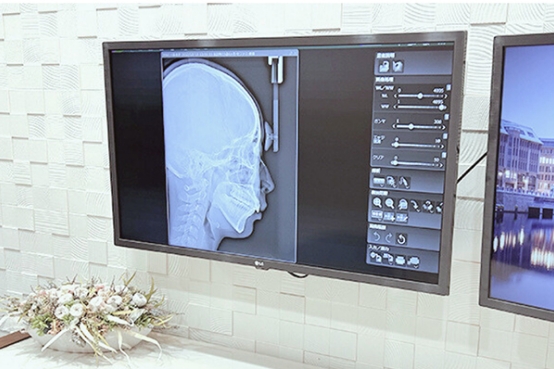

顎変形症とは、あごの骨に骨格的な問題があり、前後・左右・上下にずれることで噛み合わせや顔貌に悪影響を及ぼしている状態です。

歯列矯正治療のみでは噛み合わせを改善できないので、顎変形症手術を併用して骨の大きさの不調和を整え、良好な噛み合わせへと改善します。

手術を伴う矯正治療(外科的矯正治療)を行うと決まった時点で保険適応となります。 具体的には、重度の出っ歯・受け口・開咬・顎のゆがみ・顔貌の非対称などです。

外科的矯正治療を受けることができる施設は限られており、 “顎口腔機能診断施設” の指定を受けた歯科医院でのみ可能です。